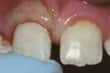

門牙碎裂 |